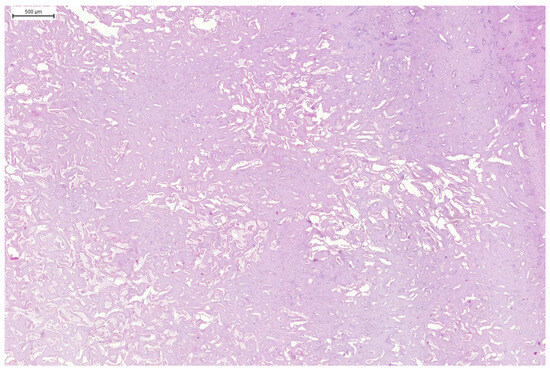

3.3. Results of Microscopic Examination